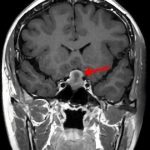

断層撮影

手術前2